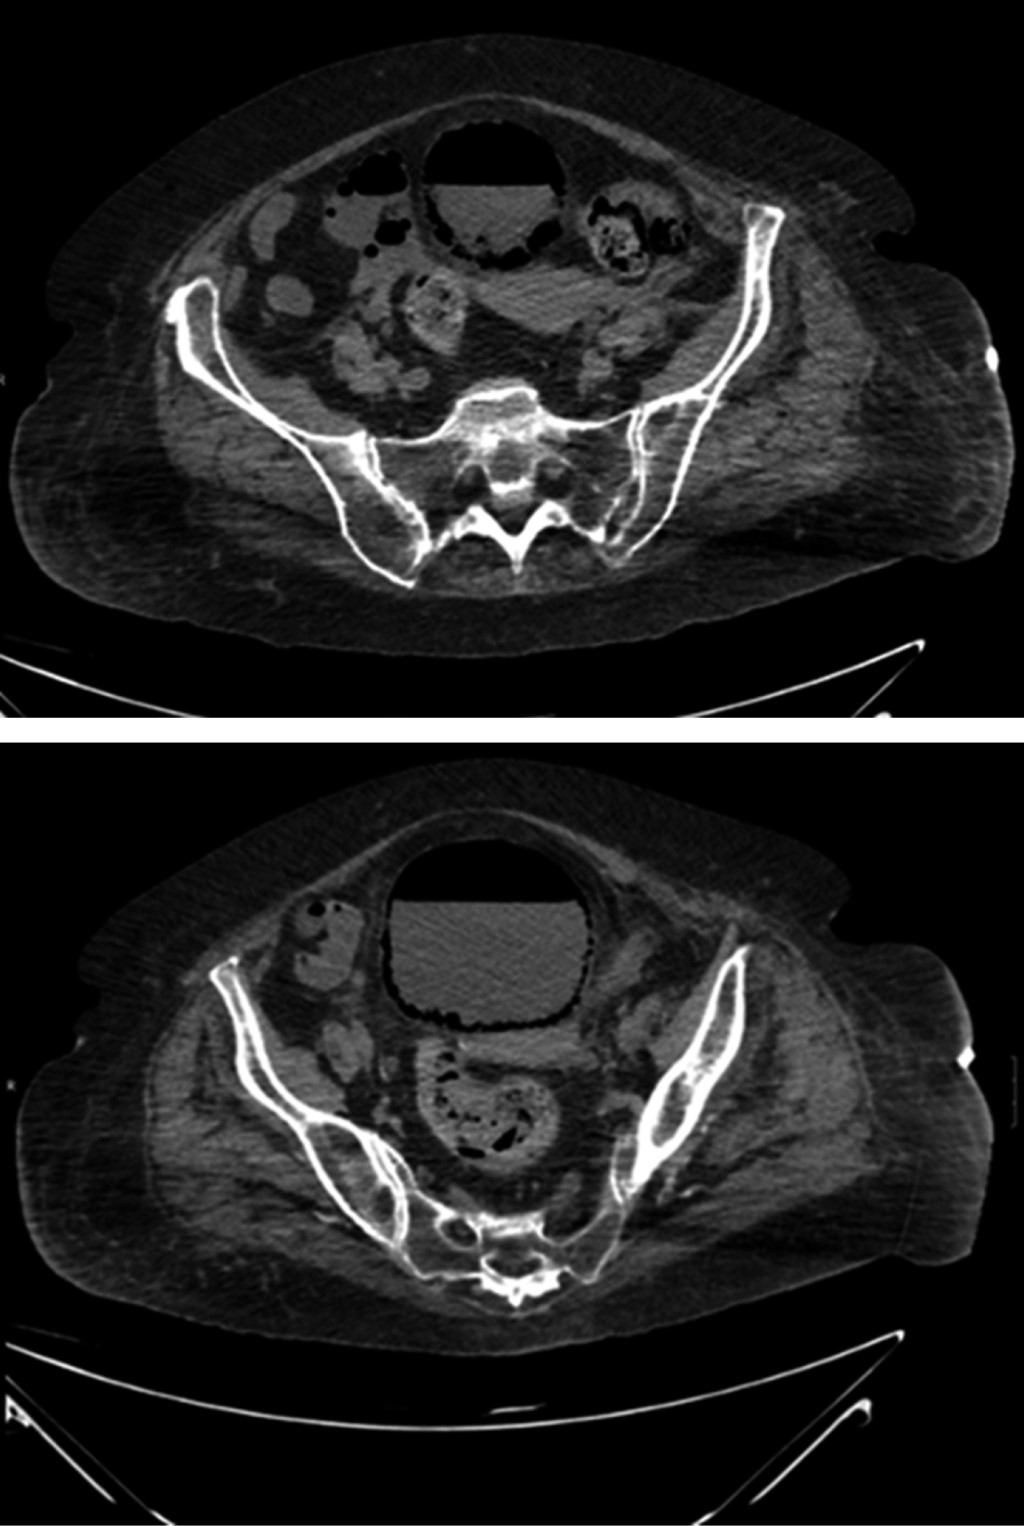

Se sospecha foco abdominal por lo que se realiza angiotomografía computarizada abdominal observándose globo vesical con burbujas de aire intraparietal a nivel de pared posterolateral derecha que corresponde con cistitis enfisematosa con trabeculación de la grasa perivesical subyacente.

El diagnóstico se basa en la historia clínica y alta sospecha en pacientes de riesgo. Los hallazgos radiológicos son esenciales. Los análisis de orina revelan piuria y hematuria, con urocultivos y hemocultivos generalmente positivos.5 Las pruebas radiológicas muestran gas (Figura 1), siendo la tomografía axial computarizada (TAC) (Figura 2) la más efectiva.

La radiografía simple de abdomen evidencia una línea radiolúcida que rodea la pared vesical, correspondiendo a un nivel hidroaéreo o una imagen esférica completa que insinúa a la silueta vesical. La ecografía puede mostrar un engrosamiento parietal vesical con un patrón hiperecogénico y de "imagen sucia".